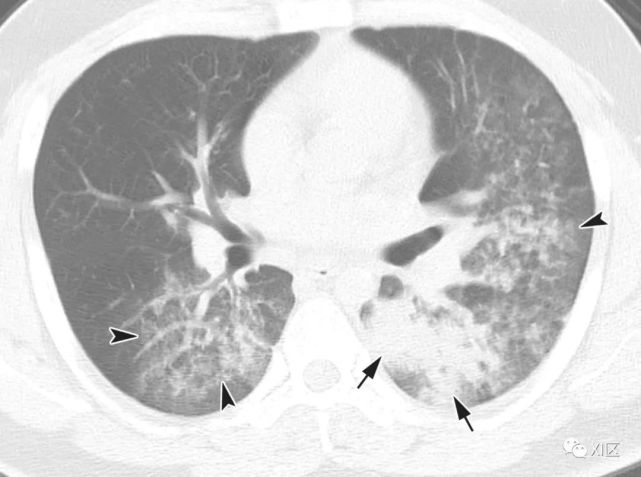

图14 一位22岁女性感染前1个月因急性淋巴细胞白血病接受单倍体相合骨髓移植治疗,有发热,诊断为 HPIV病毒性肺炎。

在主支气管水平(上)和叶间区水平(中上)的初始轴位胸部CT图像显示沿支气管血管束和轻度支气管壁增厚(箭头)的多灶性不明确结节性GGO病变(箭)。中性粒细胞减少持续存在。(中下,下)随访10天后获得的轴位胸部CT图像显示病变的范围和强度增加,并沿支气管血管束增加不规则的实变结节(箭)。尽管进行了重症监护,该患者仍然死亡。

Koo H J , Lim S , Choe J , et al. Radiographic and CT Features of Viral Pneumonia[J]. Radiographics, 2018, 38(3):719-739.